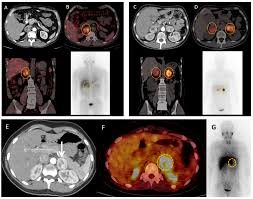

Advanced stage neuroendocrine tumors

MIBG Therapy for pheochromocytoma and paragangliomas